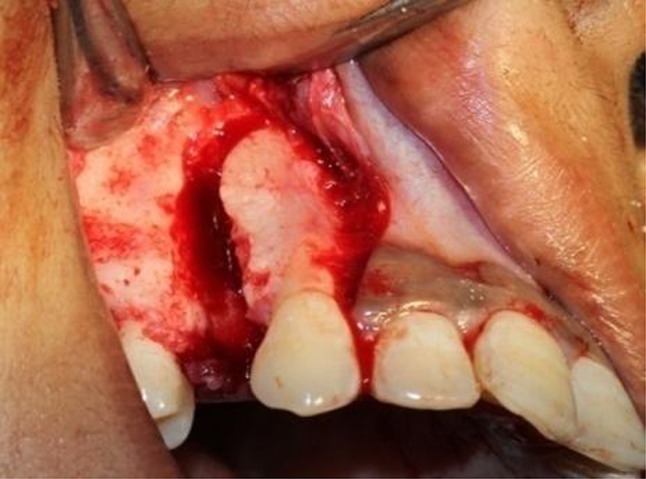

For PLD side crevicular incisions were made extending from mesial interdental papilla of 2nd premolar to the distal interdental papilla of the lateral incisor with a vertical releasing incision on either side into the veatibule placed to raise mucoperiosteal flap 6 mm above the canine and first premolar to allow for the planned undermining of the interdental septa (Fig. 2). After the first premolar extraction, the interseptal bone distal to the canine was undermined with a straight fissure bur, grooving vertically inside the extraction socket along the buccal and palatal sides, and extending obliquely toward the base of the interseptal bone to weaken its resistance (Figs. 3, 4). The depth of the undermining grooves was dependent on the thickness of the interseptal bone, as revealed on the periapical films.

Fig. 3.

Undermining interseptal bone distal to canine